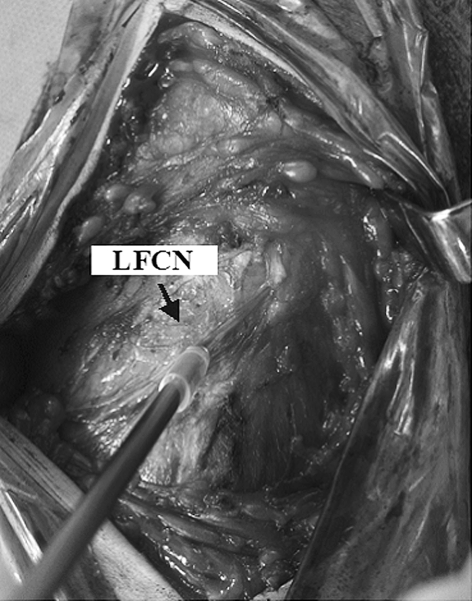

Fig. 1.

Intraoperative measurements of nerve blood flow. The measurements were performed before and after osteotomy at the point 1 cm distal from the lower border of the inguinal ligament